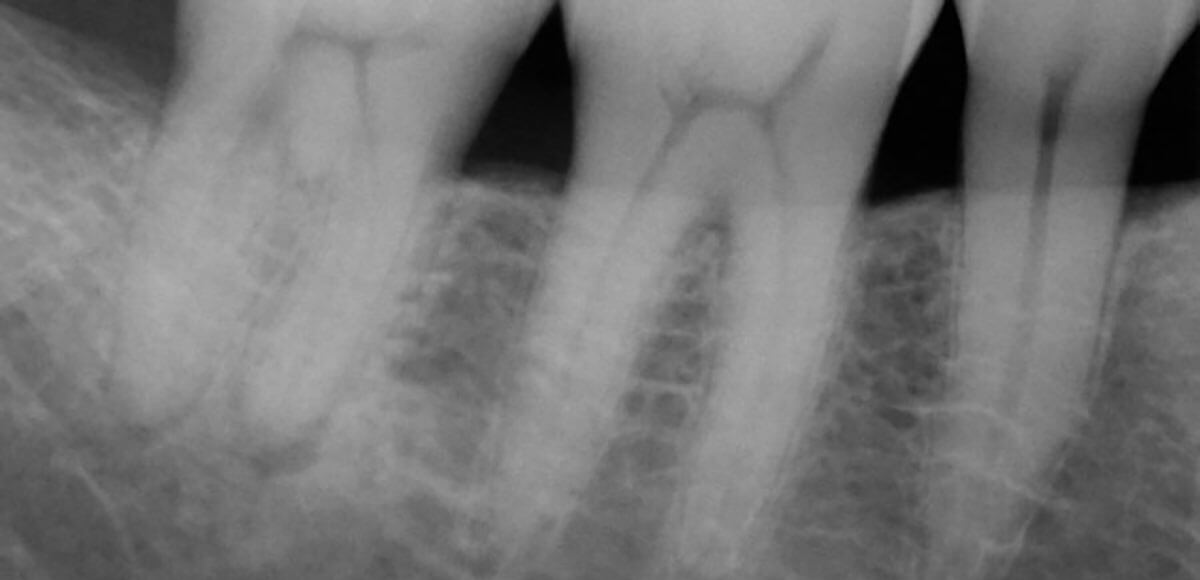

Cracked teeth — how to detect for the best prognosis